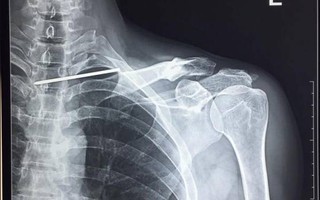

(NLĐO)- Một nam giới bị chiếc đinh dài 12 cm chọc xuyên qua đỉnh phổi, tuỷ sống vừa được các bác sĩ Bệnh viện đa khoa Đức Giang, Hà Nội cứu sống ngoạn mục. Đây là ca bệnh cực kỳ hy hữu, trên thế giới đến nay mới có 11 ca được báo cáo.